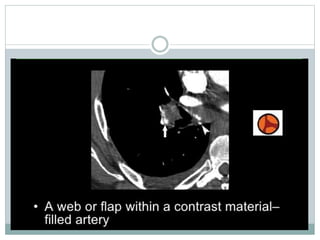

• Positive result is a filling defect or sharp cutoff in a pulmonary

artery branch